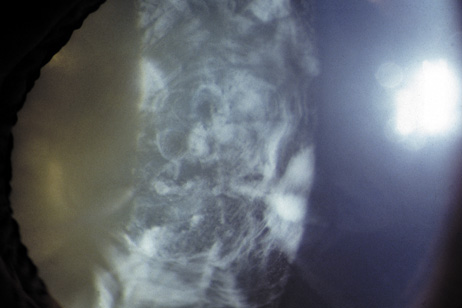

In general, patients with DM2 show less anticipation and a milder phenotype, and lack a congenital form. Affected individuals (DM1 and DM2) present with myotony and a characteristic pattern of weakness involving the facial, neck flexor, finger flexor, and hip girdle muscles. Severe arrhythmias or progressive cardiomyopathy may be fatal. Hypotestosteronism and oligospermia in males, and insulin insensitivity are frequent endocrinologic features. A specific set of serological changes is present, which includes low γ-globulin, elevated creatine kinase, and elevated follicle stimulating hormone (FSH) in males. In young adults, dust- and flake-like iridescent and highly refractile multicolored “needles” crisscross the anterior and posterior cortexes of the lens (the so-called “christmas-tree cataract”). The colors vary according to the angle of the incident light, and only a dim outline of the cataract is seen under retroillumination (Figs. 6 and 7). Under the scanning electron microscope the needles are smooth, rectangular, plate-like elements that are bordered by membranes and amorphous material, and run crisscross through the lens. The needles have a high sulfur content and pronounced S-S, CS-SC, and C-S vibrations under energy-dispersive x-ray and Raman microanalysis.34 They increase and accumulate with age, and may eventually result in a mature cataract. Rarely, macular and tapeto-retinal pigment epithelial degeneration, and optic atrophy are associated with DM.

Fig. 7. Christmas-tree cataract. Dust- and flake-like iridescent and highly refractile multicolored “needles” crisscross the anterior lens cortex in a patient with DM.